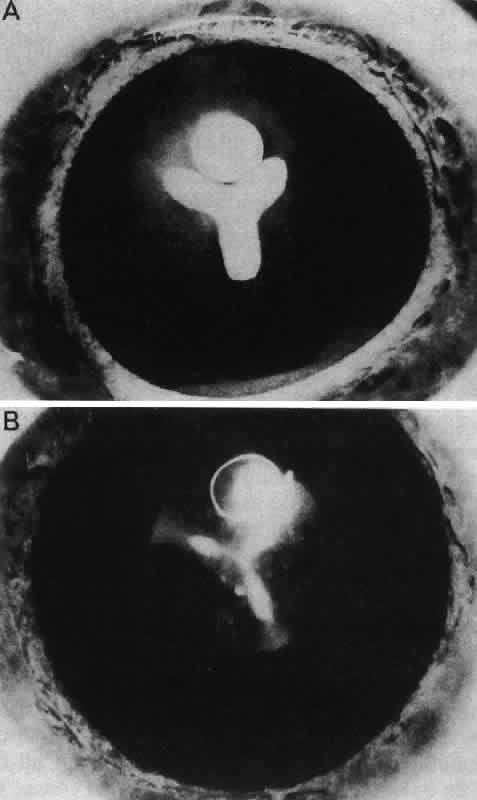

Other opacities that fall under the category of capsulolenticular cataracts are the polar cataracts. In this case, the opacities are situated at either pole of the lens and generally involve only the superficial cortical area. The relatively common anterior variety assumes a number of forms but is typically plaquelike and circumscribed. The size of the opacity may vary from a small dot to one that occupies the entire pupillary region. Because it may have a laminate appearance, it has also been called a pyramidal cataract. Similar opacities are observed in children who have had corneal ulcers during infancy. The fact that the fetal nucleus of the lens is not involved suggests an occurrence relatively late in intrauterine life. Occasionally, an opacity might be seen above the previously incurred derangement separated by an apparently normal lenticular zone, producing the so-called reduplicated cataract. In this case, it is believed that, following an initial disturbance, normal fibers are deposited, followed later by a new, sometimes more severe disturbance that produces a second region of opacification. There are a number of variations on this theme, and such opacities may assume myriad possible forms. It may be significant that these opacities are often associated with a strand or strands of pupillary membrane that bridge the iris (in the region of the collarette) to the polar cataract.181–183 Similar adhesions to the pupillary margin have been noted. Another observation has been that these cataracts are often associated with signs of keratitis, most notably corneal opacification. It is interesting that, histologically, the changes are similar to those observed in the adult human lens following corneal ulceration.177–180 The polar cataract is typically associated with a hyperplasia of the epithelium and a great deal of necrosis of lens fibers in the subepithelial area.184 Multistratification of the epithelium occurs as the cells fill a depression left by the necrotic fibers (Figs. 36 AND 37). The cells become spindle-shaped and produce PAS-positive material. Contrary to a long-held but erroneous notion, the plaque thus formed does not represent a metaplastic transformation of epithelial cells into fibroblasts.185 The plaque is often undermined by normal cuboidal epithelial cells and is eventually surrounded by capsulelike material (see Figs. 36 AND 37). The most reasonable explanation of the basis of this anomaly is the development of intrauterine inflammation. Although it has been suggested that the anterior polar cataract may be the result of a persistent vascular tunic that interferes with nutrition, the counterpart, the posterior polar cataract, need not be associated with hyaloid remnants, yet the histologic picture is quite similar.

Fig. 36. Photomicrographs of the development of anterior subcapsular cataract. A. The beginning of multistratification of the anterior epithelium, owing to localized hyperplasia of the lens epithelial cells. B. Further stratification of the epithelium, with denucleation occurring in some of the cells. C. The final stage of cataract formation showing the so-called fibrous plaque (F), bounded on the anterior and posterior sides with capsule material. Beneath the posterior capsule (C) a newly formed epithelial population can be seen (E). (Yanoff M, Fine BS: Ocular Pathology. New York, Harper & Row, 1975)

Fig. 37. Development of anterior polar cataract: schematic illustration of the sequence of events described in Figure 36. (Font RI, Brownstein S: A light and electron microscopic study of anterior subcapsular cataracts. Am J Ophthalmol 78:972, 1974)